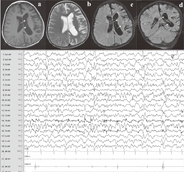

患儿,女,6岁,因间断抽搐一年半,加重20 d入院。一年半前患儿无明显诱因出现抽搐,初表现为意识清楚,右侧口角抖动,持续约2 min缓解,共5次,后抽搐表现为意识丧失,头后仰,双眼上翻,口吐白沫,四肢强直抖动,持续3~20 min不等,最多时每日抽搐10余次,期间出现1次右侧肢体Todd麻痹,持续约3 h后缓解。先后就诊于多家医院,神经系统查体未见异常,行脑电图检查示:异常脑电图,清醒-睡眠各期左侧额极、额区可见大量的棘慢波活动,可向颞区泛化,磁共振头部平扫正常。临床诊断为癫痫。给予口服抗癫痫药物治疗,初口服拉莫三嗪[0.3 mg/(kg·d)]5 d,家长自行停药,后口服奥卡西平[10 mg/(kg·d)]1周,因控制不理想停用,后加用德巴金[30 mg/(kg·d)]、左乙拉西坦[30 mg/(kg·d)],仍间断有抽搐发作,有时表现为全身强直阵挛发作,有时表现为意识丧失,双眼凝视,右下肢抖动,持续约1~2 min自行缓解,多出现于入睡或睡醒后,期间最长2个月无发作,平均每月发作2~9次,家长反复就诊,曾加用妥泰、氯硝西泮、中药制剂(具体描述不清)等,抽搐控制不佳。入院前20 d抽搐加重,表现为意识清楚,头向右侧晃动,右侧眼睑、口角、右侧肢体持续性抖动,伴右侧肢体活动不灵,表现为右上肢上抬无力,走路蹒跚,在当地医院调整左乙拉西坦[75 mg/(kg·d)]和德巴金[50 mg/(kg·d)]剂量,抽搐未见好转,家长诉患儿记忆力较前下降,无发热,无吐泻,故来我科。既往史:出生史及生长发育史正常,否认癫痫家族史。查体:一般状态可,神志清楚,问话可答,无颅神经瘫,咽无充血,心肺腹部查体未见明显异常,脑膜刺激征阴性,右上肢肌力Ⅲ级,右下肢肌力Ⅳ级,左侧肢体肌力正常,右侧膝腱反射减弱,左侧膝腱反射正常,双侧巴氏征未引出。辅助检查:血常规、超敏C-反应蛋白、肝功、肾功、心肌酶、血气分析、抗核抗体未见异常。血尿代谢筛查未见异常,丙戊酸浓度48.4 μg/ml(参考值:50~100 μg/ml),左乙拉西坦3.4 μg/ml(参考值:12~46 μg/ml)。磁共振头部平扫提示左侧脑萎缩(图1)。长程脑电图(图1):异常脑电图,双侧半球不对称,左侧波幅高、放电多,左侧前头部及中央为主慢波夹杂多灶性尖波、(多)尖慢波接近持续发放伴频繁节律性或非节律性局部肌阵挛发作,监测到多次左侧Rolandic区或后头部起始部分性发作及电发作。韦氏学龄前及入学儿童智力测查:言语智商86、操作智商82、总智商82,均低于正常水平。临床诊断为Rasmussen综合征。治疗上未调整抗癫痫药物剂量,建议加用激素和丙种球蛋白或手术治疗,家长未同意,自行出院。随访3个月,患儿表现同前,右侧肢体瘫痪无明显加重,未复查磁共振头部平扫及长程脑电图。

a.横断面T1WI,b.横断面T2WI,c.横断面FLAIR,d.冠状位FLAIR,e.长程脑电图;左侧大脑半球脑回变细,脑沟增多、加深,左侧脑室扩张,形态欠规则;异常脑电图,双侧半球不对称,左侧波幅高、放电多,左侧后头部或Rolandic区为主慢波夹杂多灶性尖波、(多)尖慢波接近持续发放。